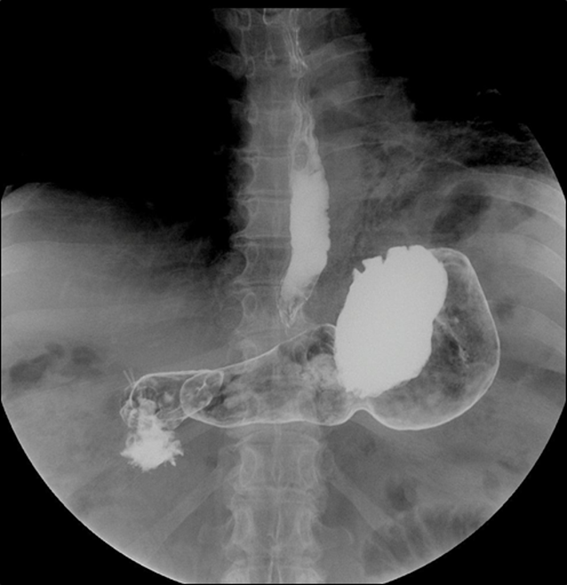

Mujer de 63 años, casada, ama de casa, procedente de la amazonía peruana. No presenta antecedentes patológicos. Niega tabaquismo y alcoholismo. Inició tos seca esporádica, sin fiebre ni pérdida de peso. La tos persistió y se cronifica en el tiempo. A los ocho meses de iniciado el cuadro, apareció cansancio progresivo y fatiga, por lo que acude a hospital donde el examen físico del aparato respiratorio reveló crepitantes difusos tipo velcro en 2/3 inferiores de ambos campos pulmonares. La radiografía al tórax comprobó fibrosis pulmonar, en patrón de vidrio deslustrado (figura 1).

Figura 1. Radiografía de tórax donde se aprecia patrón difuso de vidrio deslustrado en 2/3 inferiores de inferiores de ambos campos pulmonares